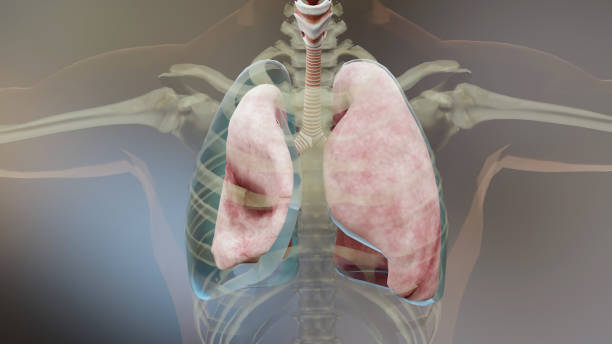

기흉(pneumothorax)은 폐와 흉부벽 사이에 공기가 쌓이는 상태를 말합니다. 이는 폐가 공기로 가득 차면서 폐가 축소되고 압축되어 발생합니다. 이러한 압축으로 인해 폐의 기능이 저하되며 호흡 곤란, 가슴 통증 등의 증상을 유발할 수 있습니다.